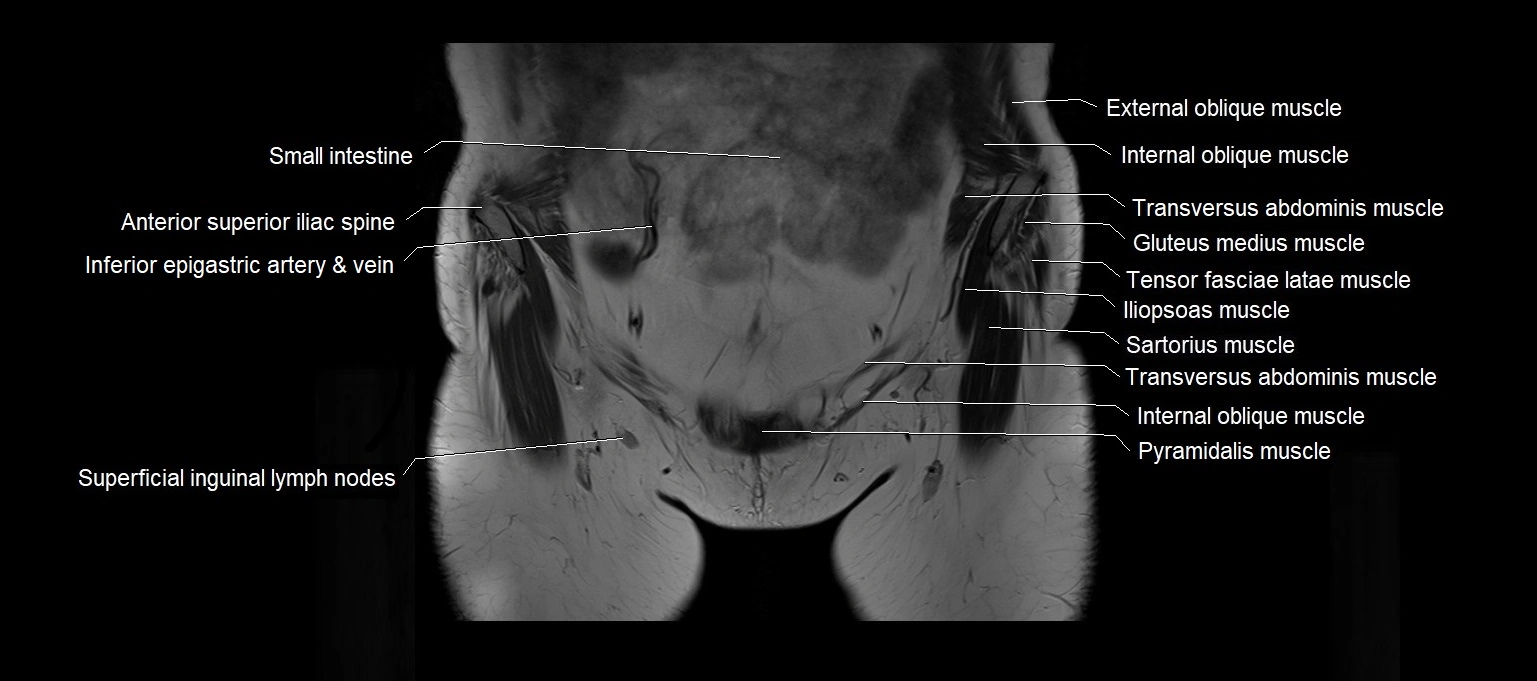

MRI images